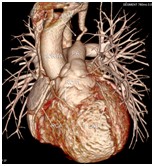

心脏大血管CT成像